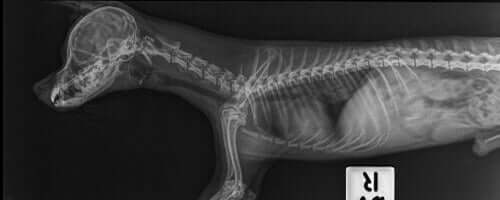

La colonna vertebrale dei cani è divisa in tre sezioni: cervicale, toracica e lombare. La sezione cervicale sostiene il cranio e le spalle del cane. Quella toracica riguarda l’area del busto, dove si trovano le costole che proteggono gli organi interni.

La sezione lombare sostiene le zampe posteriori del cane, e si allunga anche verso la coda.